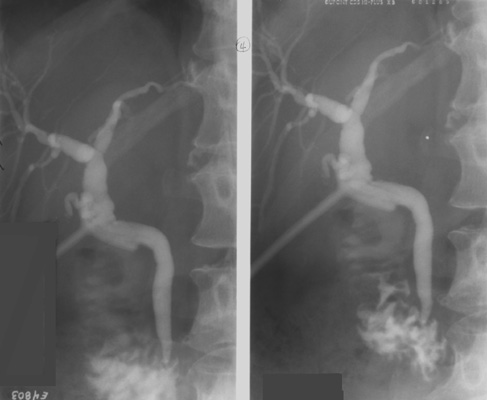

- Roll the patient to the supine position

and continue filling the ducts until the branches in the right lobe

are filled along with the extrahepatic duct. Again, take a spot image(s)

(2-on-1 format, 109 kVp). Try to time the exposure for when contrast

squirts from the common bile duct (CBD) into the duodenum.